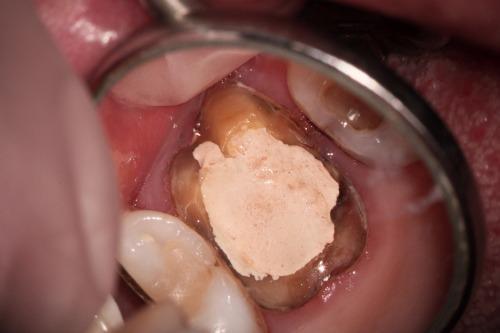

ひどい虫歯で歯がない。根管治療で歯を残せた。歯を抜かないで済んだ。

根管治療1/6 虫歯を取り除く ラバーダムとマイクロスコープを必ず使います。